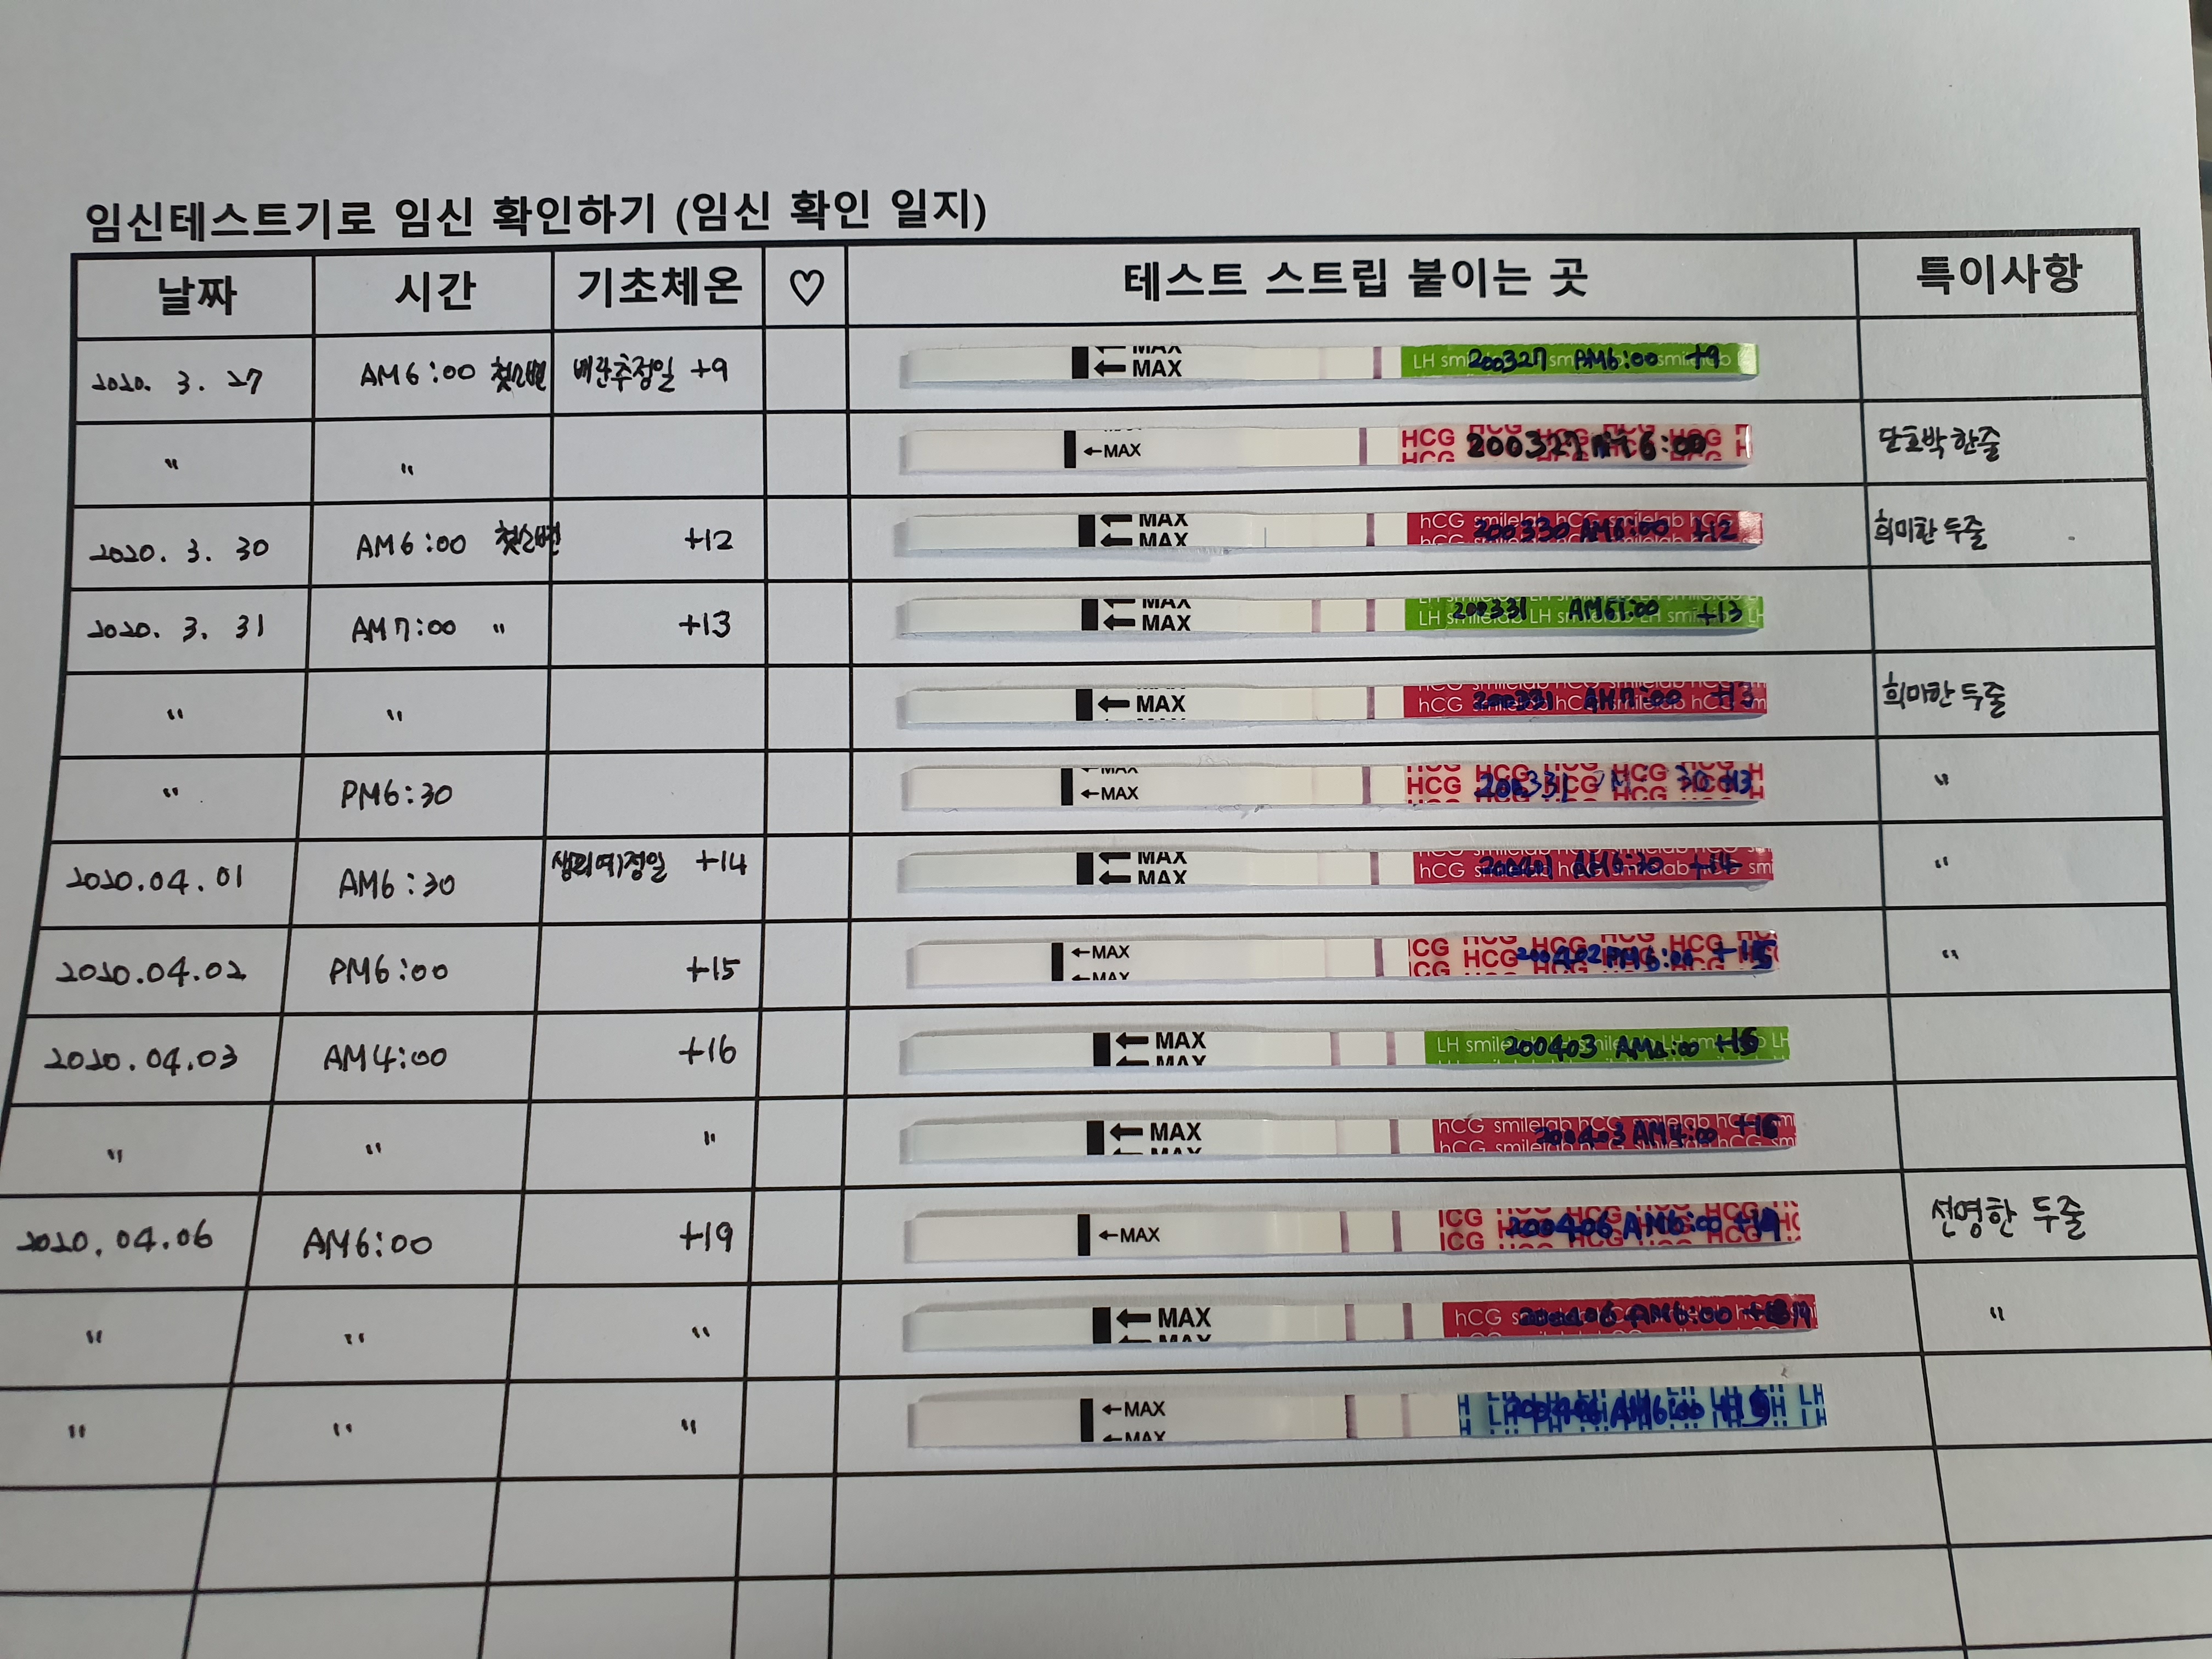

혼자 써 본 임신확인 일지 (feat.Excel)

배란추정일 9일째부터 기록한 임테기, 배테기 측정한 결과.

4월 3일 배란추정 +16일째에 한 번, 4월 6일 다시 측정 배란19일째 확인해본 결과예요.

육안으로도 두 줄이 선명하게 확인이 될 뿐만 아니라 3일 전후의 차이점이 드러나도록 밴드의 진하기가 다르지요? 저도 임신 준비하면서 이 두 줄을 얼마나 보고 싶던지.. 초초초매직이라도 나올까 반응 시간이 길어져도 뚫어져라 확인했었는데도 단호박을 먹었던 지날 시절이 떠오르네요..ㅠㅠ 둘째를 기다리는 마음이 컸던지라 더욱 더 간절했는지도 몰라요. 그러다가 이렇게 선명한 두 줄을 보니 얼마나 반가웠는지! 첫째 때는 알지 못했던 마음이 몽글몽글하게 떠오르는 느낌이예요^^

뭔가 이번엔 촉이 남달랐다고 해야하나? 배란추정 일주일째에 하루종일 아랫배가 묵직한 느낌이 들어서 뭔가 다른 때와는 다르다는 걸 느꼈어요. 그래서 배란9일째에 임테기 측정을 해 봤는데, 그 땐 단호박을 먹었지만, 3일 뒤 (배란 12일 추정) 다시 측정해보니 아주 흐릿한 두 줄을 보았고, 그날 이후로 3일간 아침마다 임테기 측정을 해 보니 흐릿하지만 지속적으로 두 줄을 보았어요.